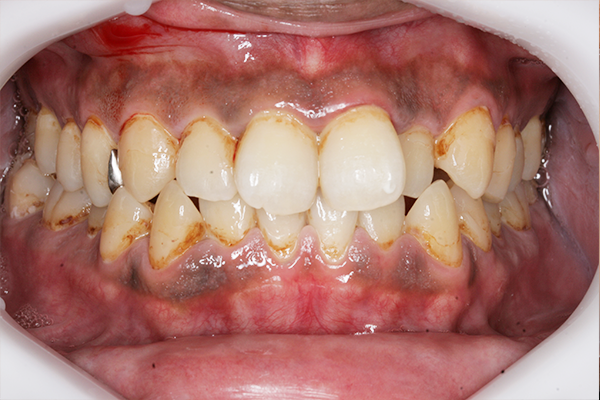

術前

術後

虫歯治療費+オフィスホワイトニング施術費(38,500円)

主訴 たばこのヤニなど全体的にきれいにしたいと来院。

むしば治療とオフィスホワイトニングを2回行い全体的に白くすることができた。

治療期間:1か月

副作用・リスク:一時的に知覚過敏の症状が出る可能性あり